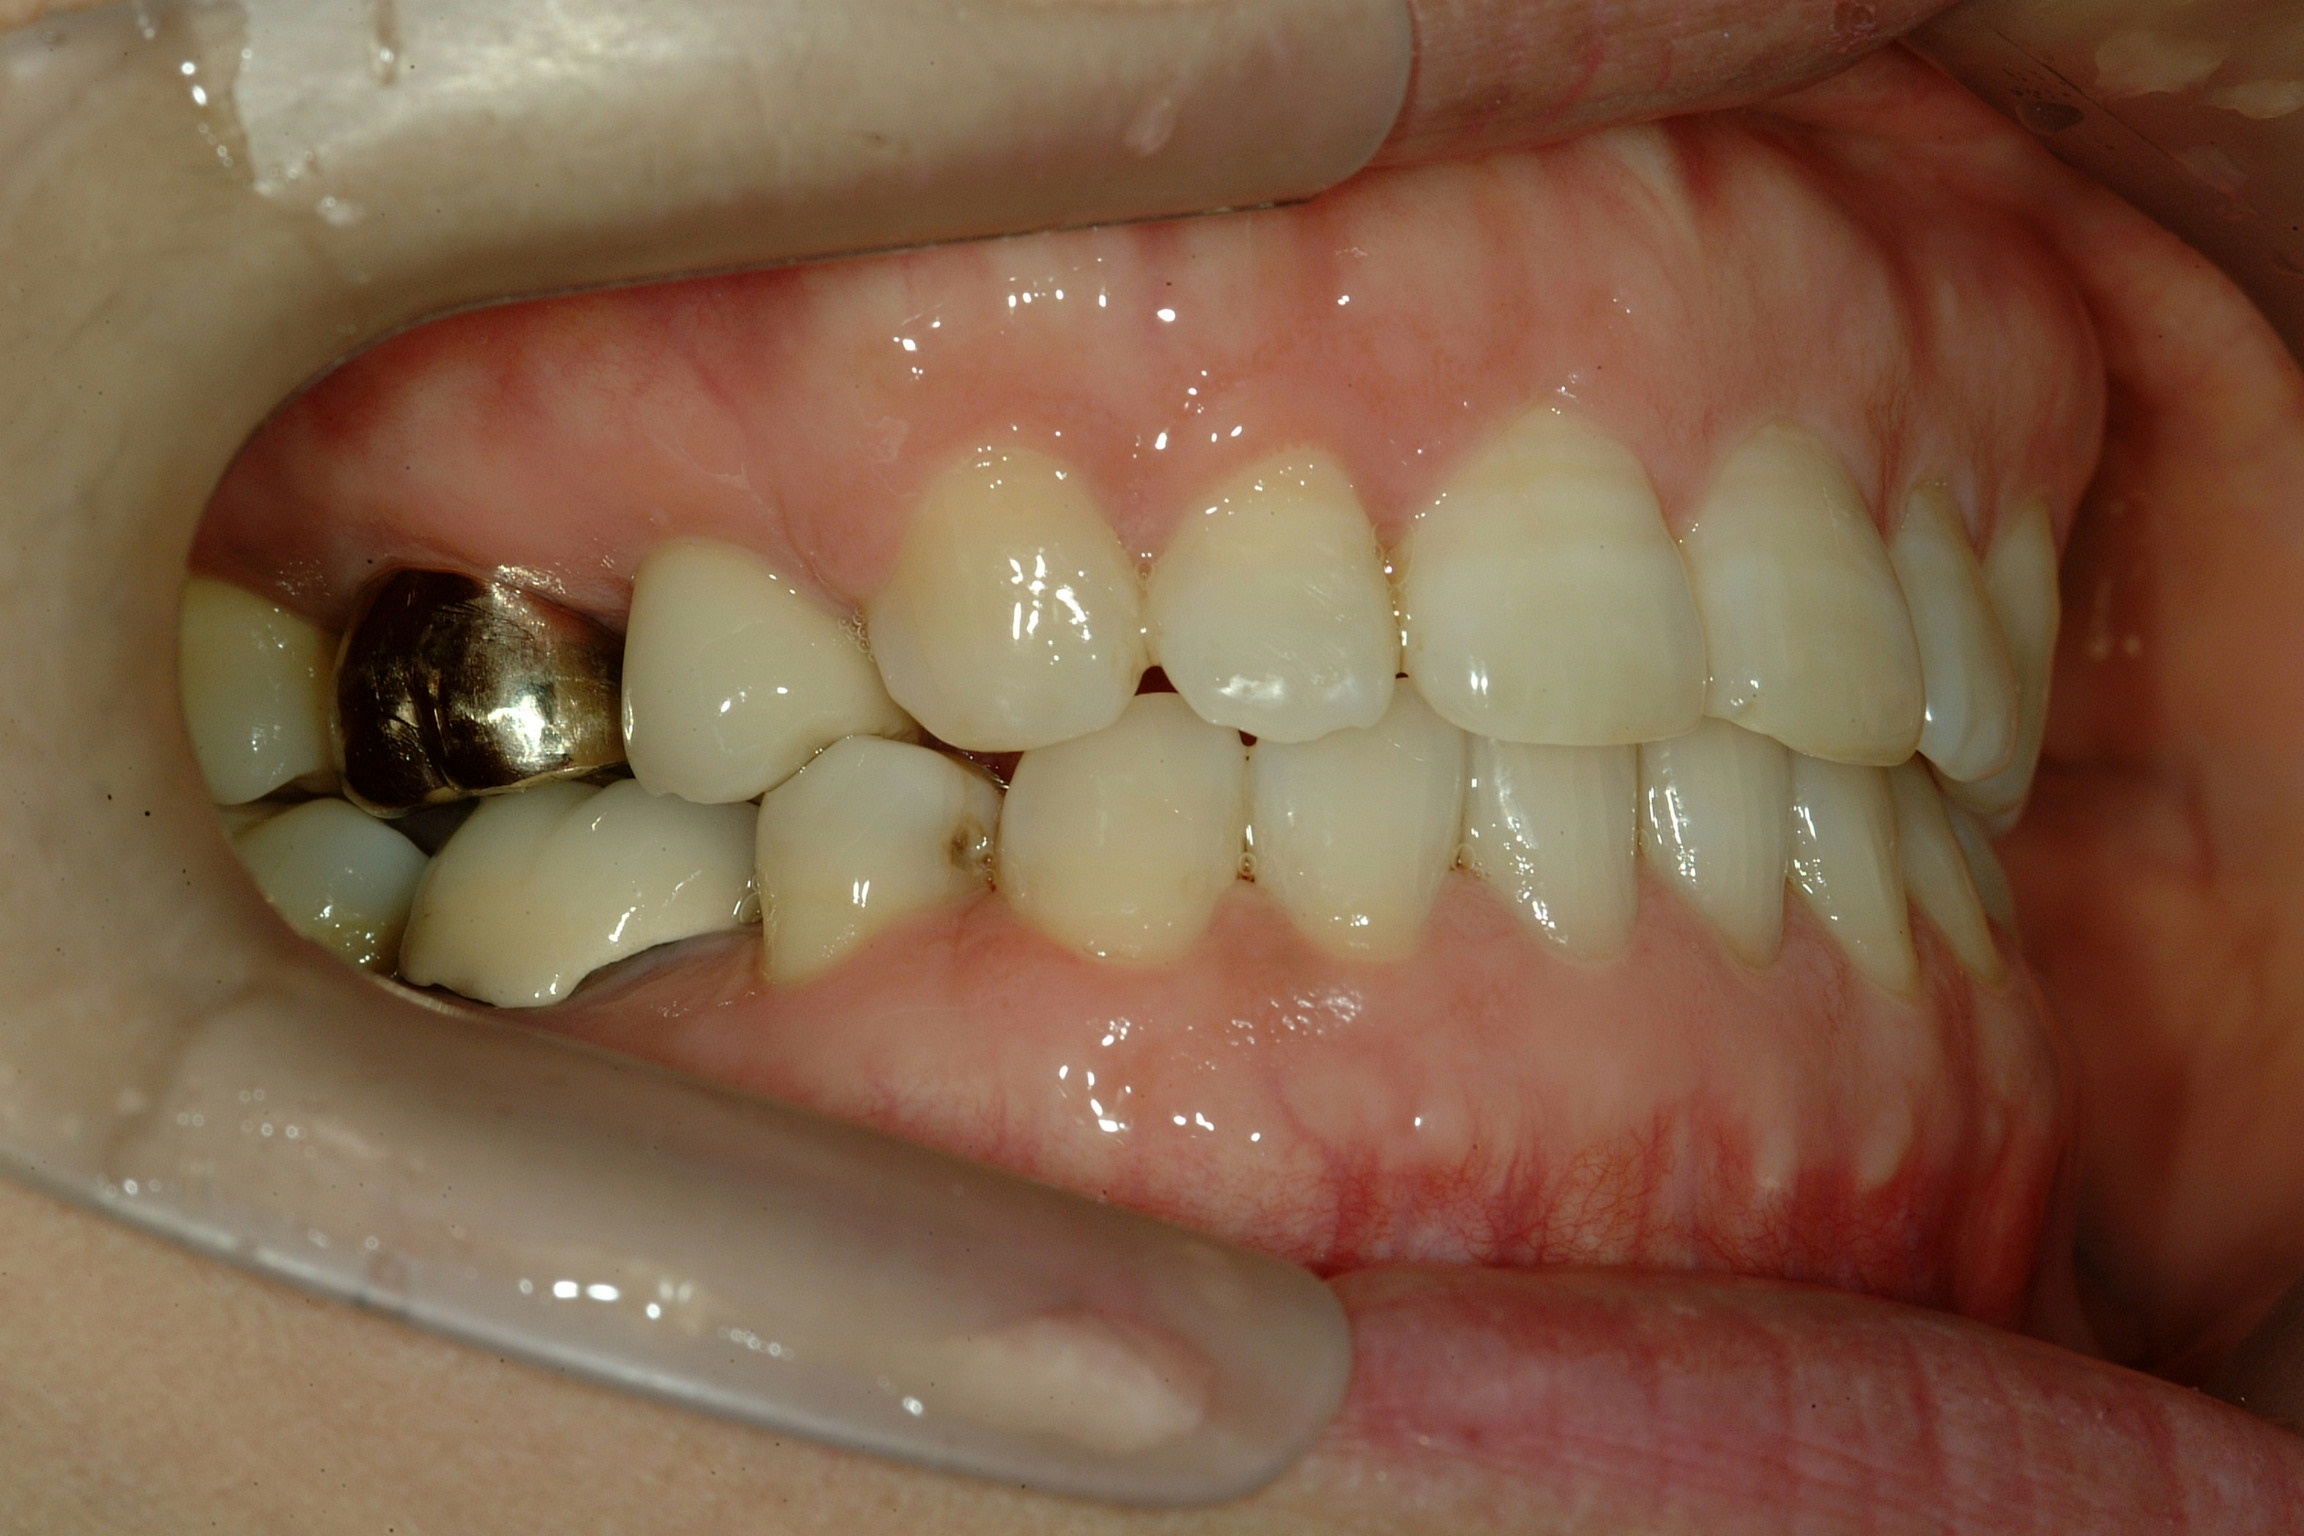

치료 전 사진입니다.